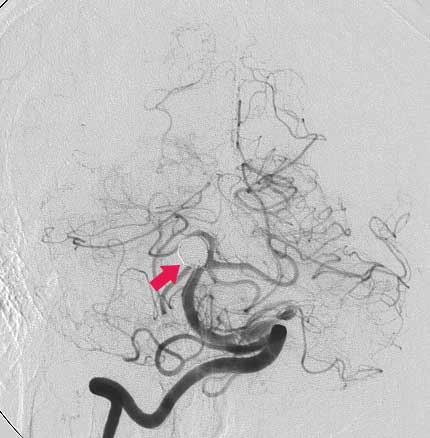

CASO 2 : Embolización endovascular con microespiras (coils) en paciente joven con hemorragia intracraneal y parálisis de nervio oculomotor

Antes de la embolización:

Después de la embolización: